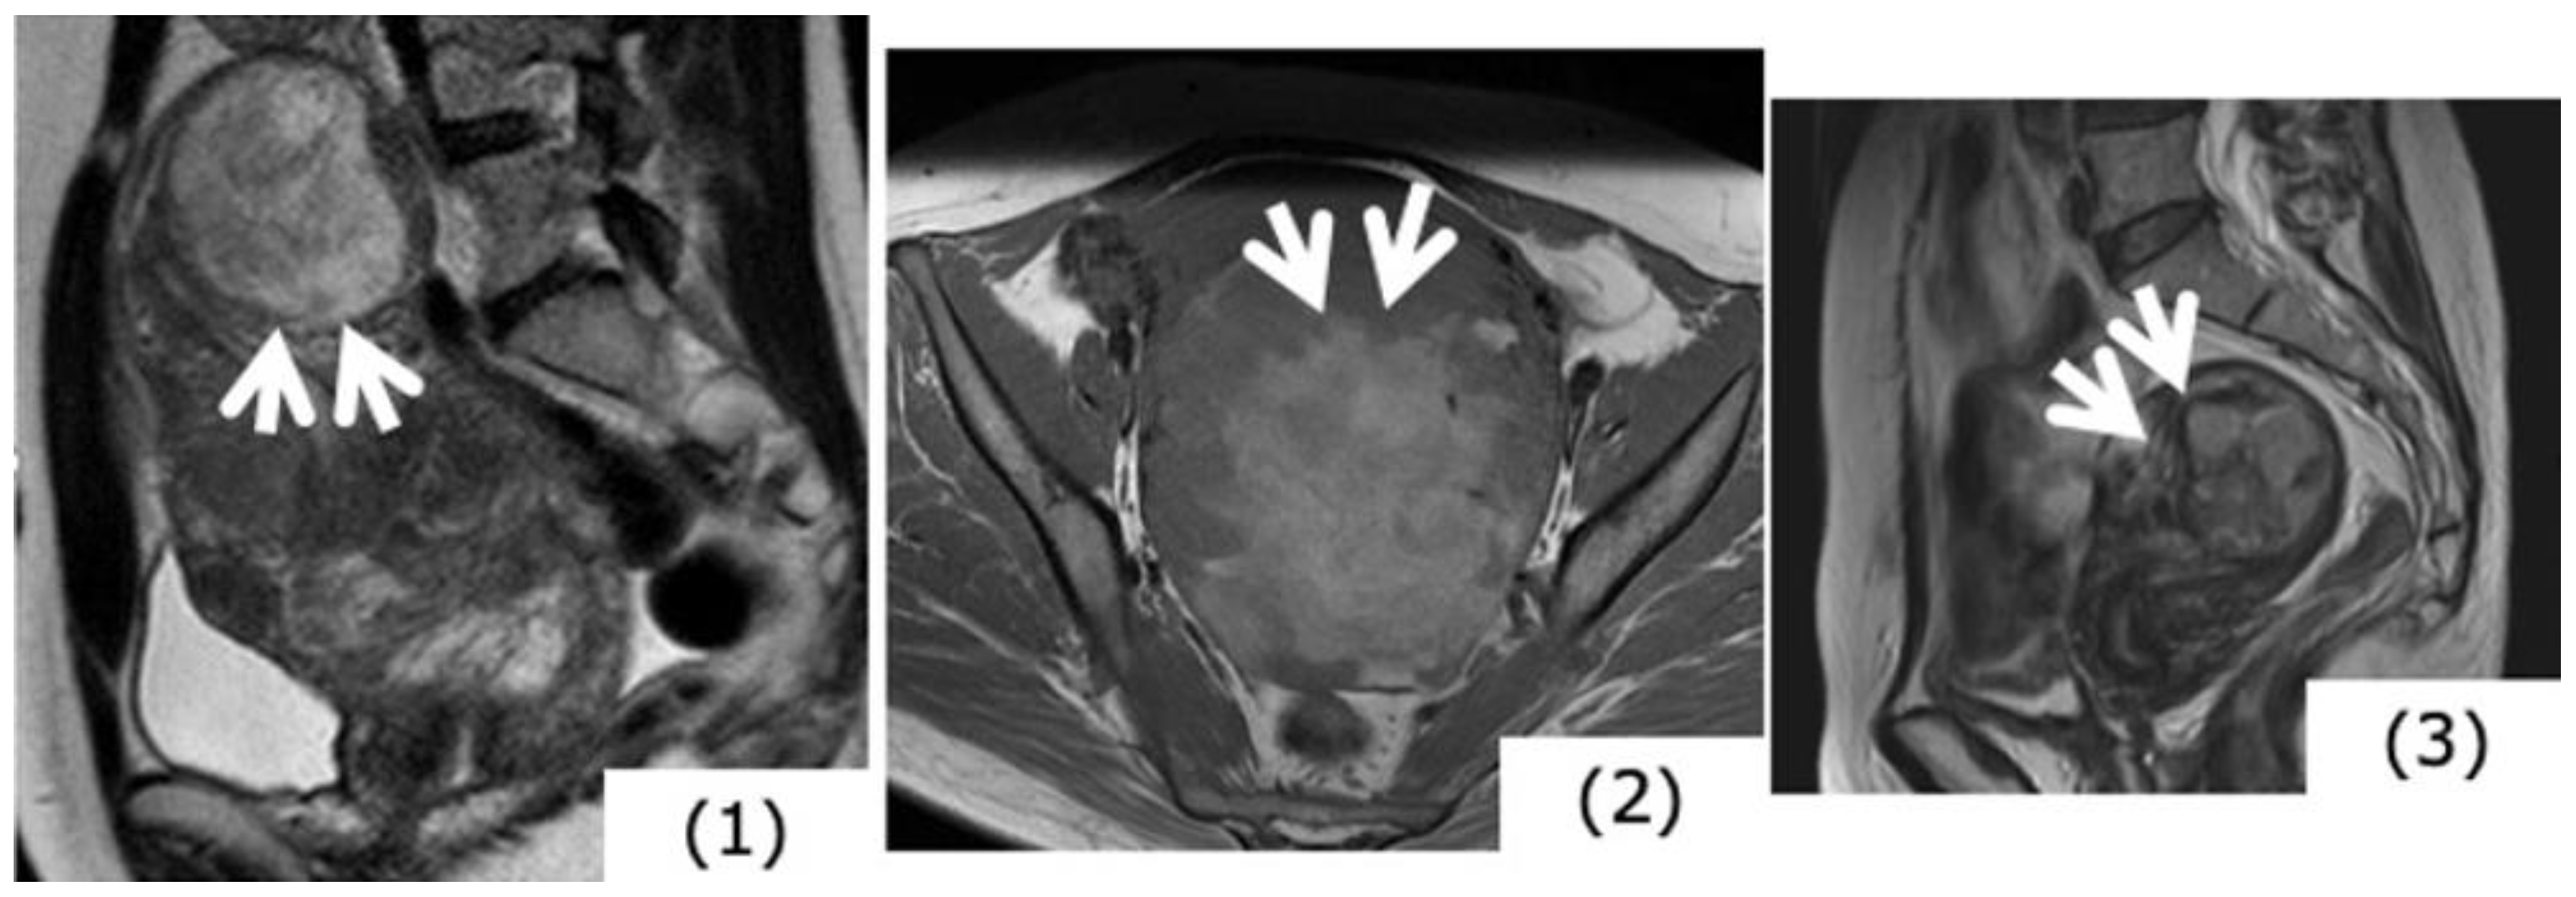

Figure 3.

Magnetic resonance image findings considered to be characteristic of (specific for) uterine sarcoma. (1) High signals in T2-weighted images (T2WI) (case of uterine myoma): Mass in the fundus uteri has extremely high signal intensity (SI). (2) High signals in T1-weighted images (T1WI) (case of uterine sarcoma): There are mottled portions of high SI suggesting hemorrhage within the mass. (3) Ill-defined mass borders (case of uterine sarcoma, T2WI): Mass existing in the myometrium. High signals are presented in T2WI, and at the arrow portions, borders are ill-defined.